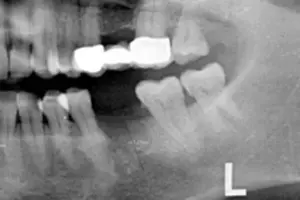

März: 8 Wochen später: Herr F. hat seinen Termin zur Implantation bei mir in der Praxis. Vor dem Eingriff habe ich bereits, anhand von Röntgenaufnahmen, überprüft, ob der vorhandene Knochen breit und tief genug ist, um ein Implantat bestimmter Länge und Durchmessers zu setzen. Siehe Bild 2.

Dies ist bei Herrn F der Fall. Somit erhält Herr F. eine kleine örtliche Betäubung, genau wie damals als der Zahn entfernt worden ist. Die örtliche Betäubung stellt sicher, dass Sie als Patient während meines Eingriffs absolut schmerzfrei bleiben. Hierüber müssen Sie sich somit keine Gedanken machen – und ich mir auch nicht. So kann ich mich zu 100% auf die professionelle Einsetzung Ihres Zahnimplantats konzentrieren.

Bild 2: Zahnlücke von fehlendem Zahn 36